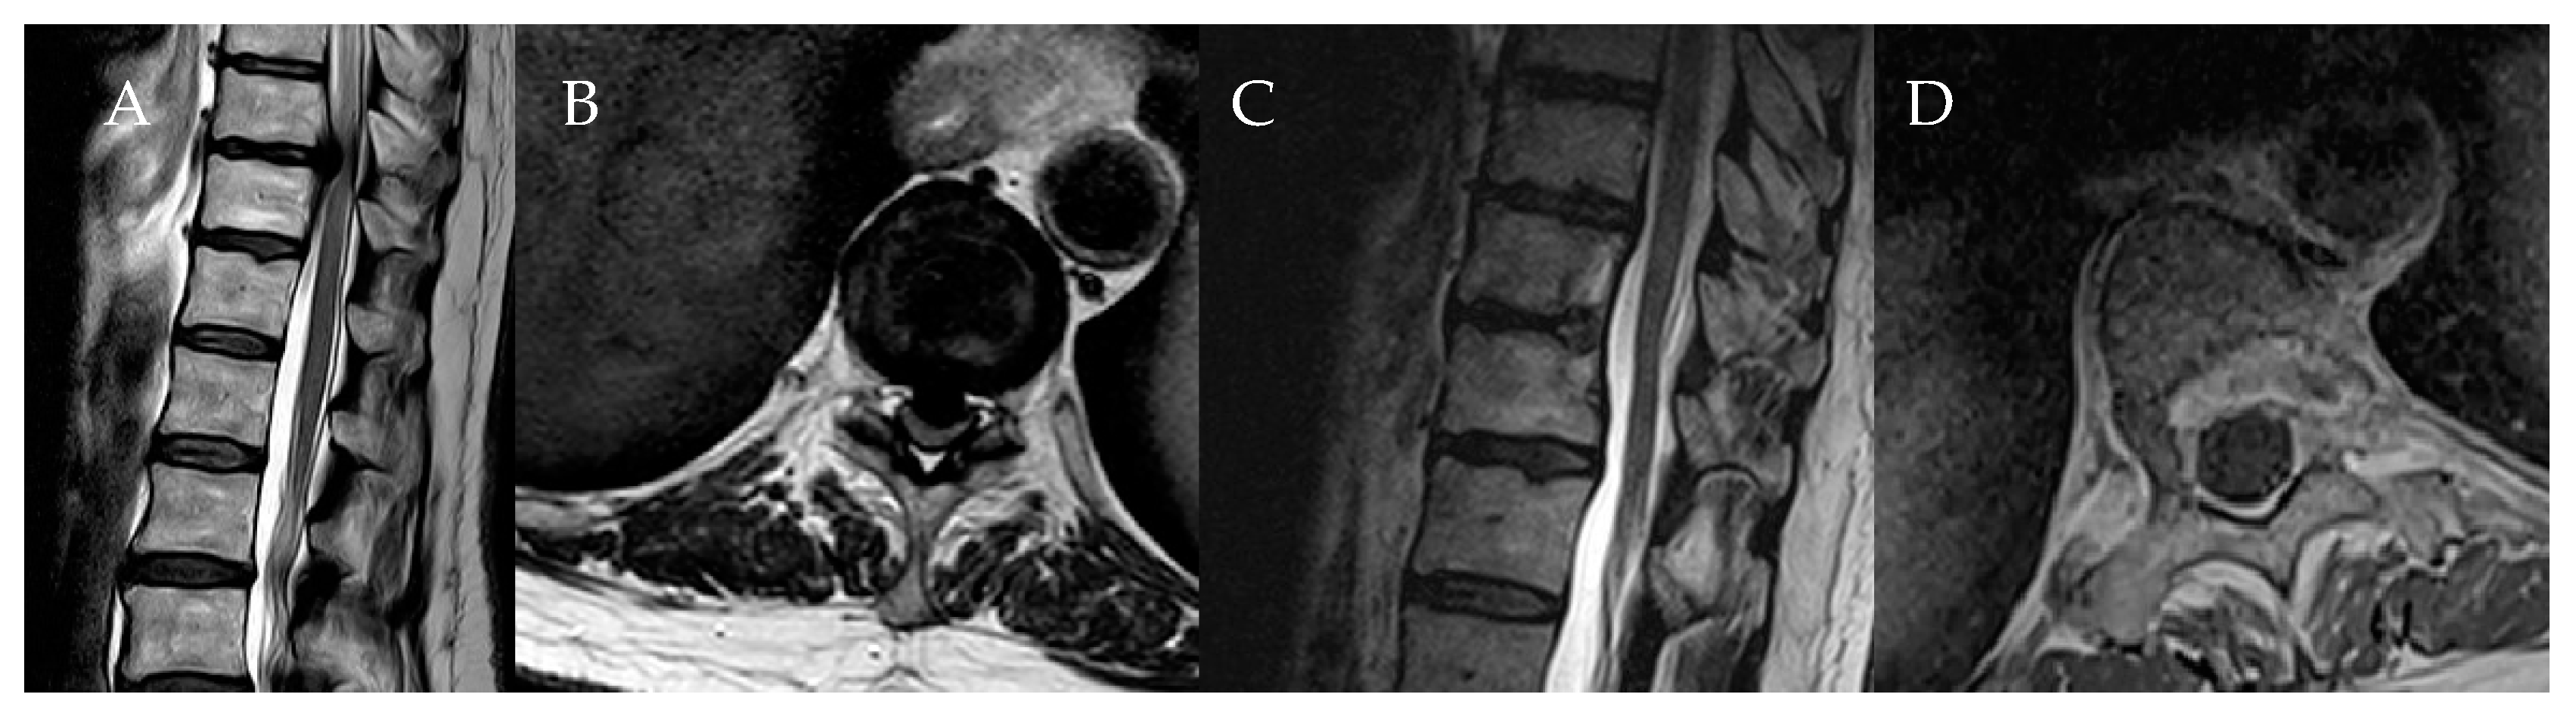

Surgical Treatment of Calcified Thoracic Herniated Disc Disease via the Transthoracic Approach with the Use of Intraoperative Computed Tomography (iCT) and Microscope-Based Augmented Reality (AR)

4. Patients

5.3. Use of Navigation and Intraoperative Imaging in the Resection of Herniated Thoracic Discs